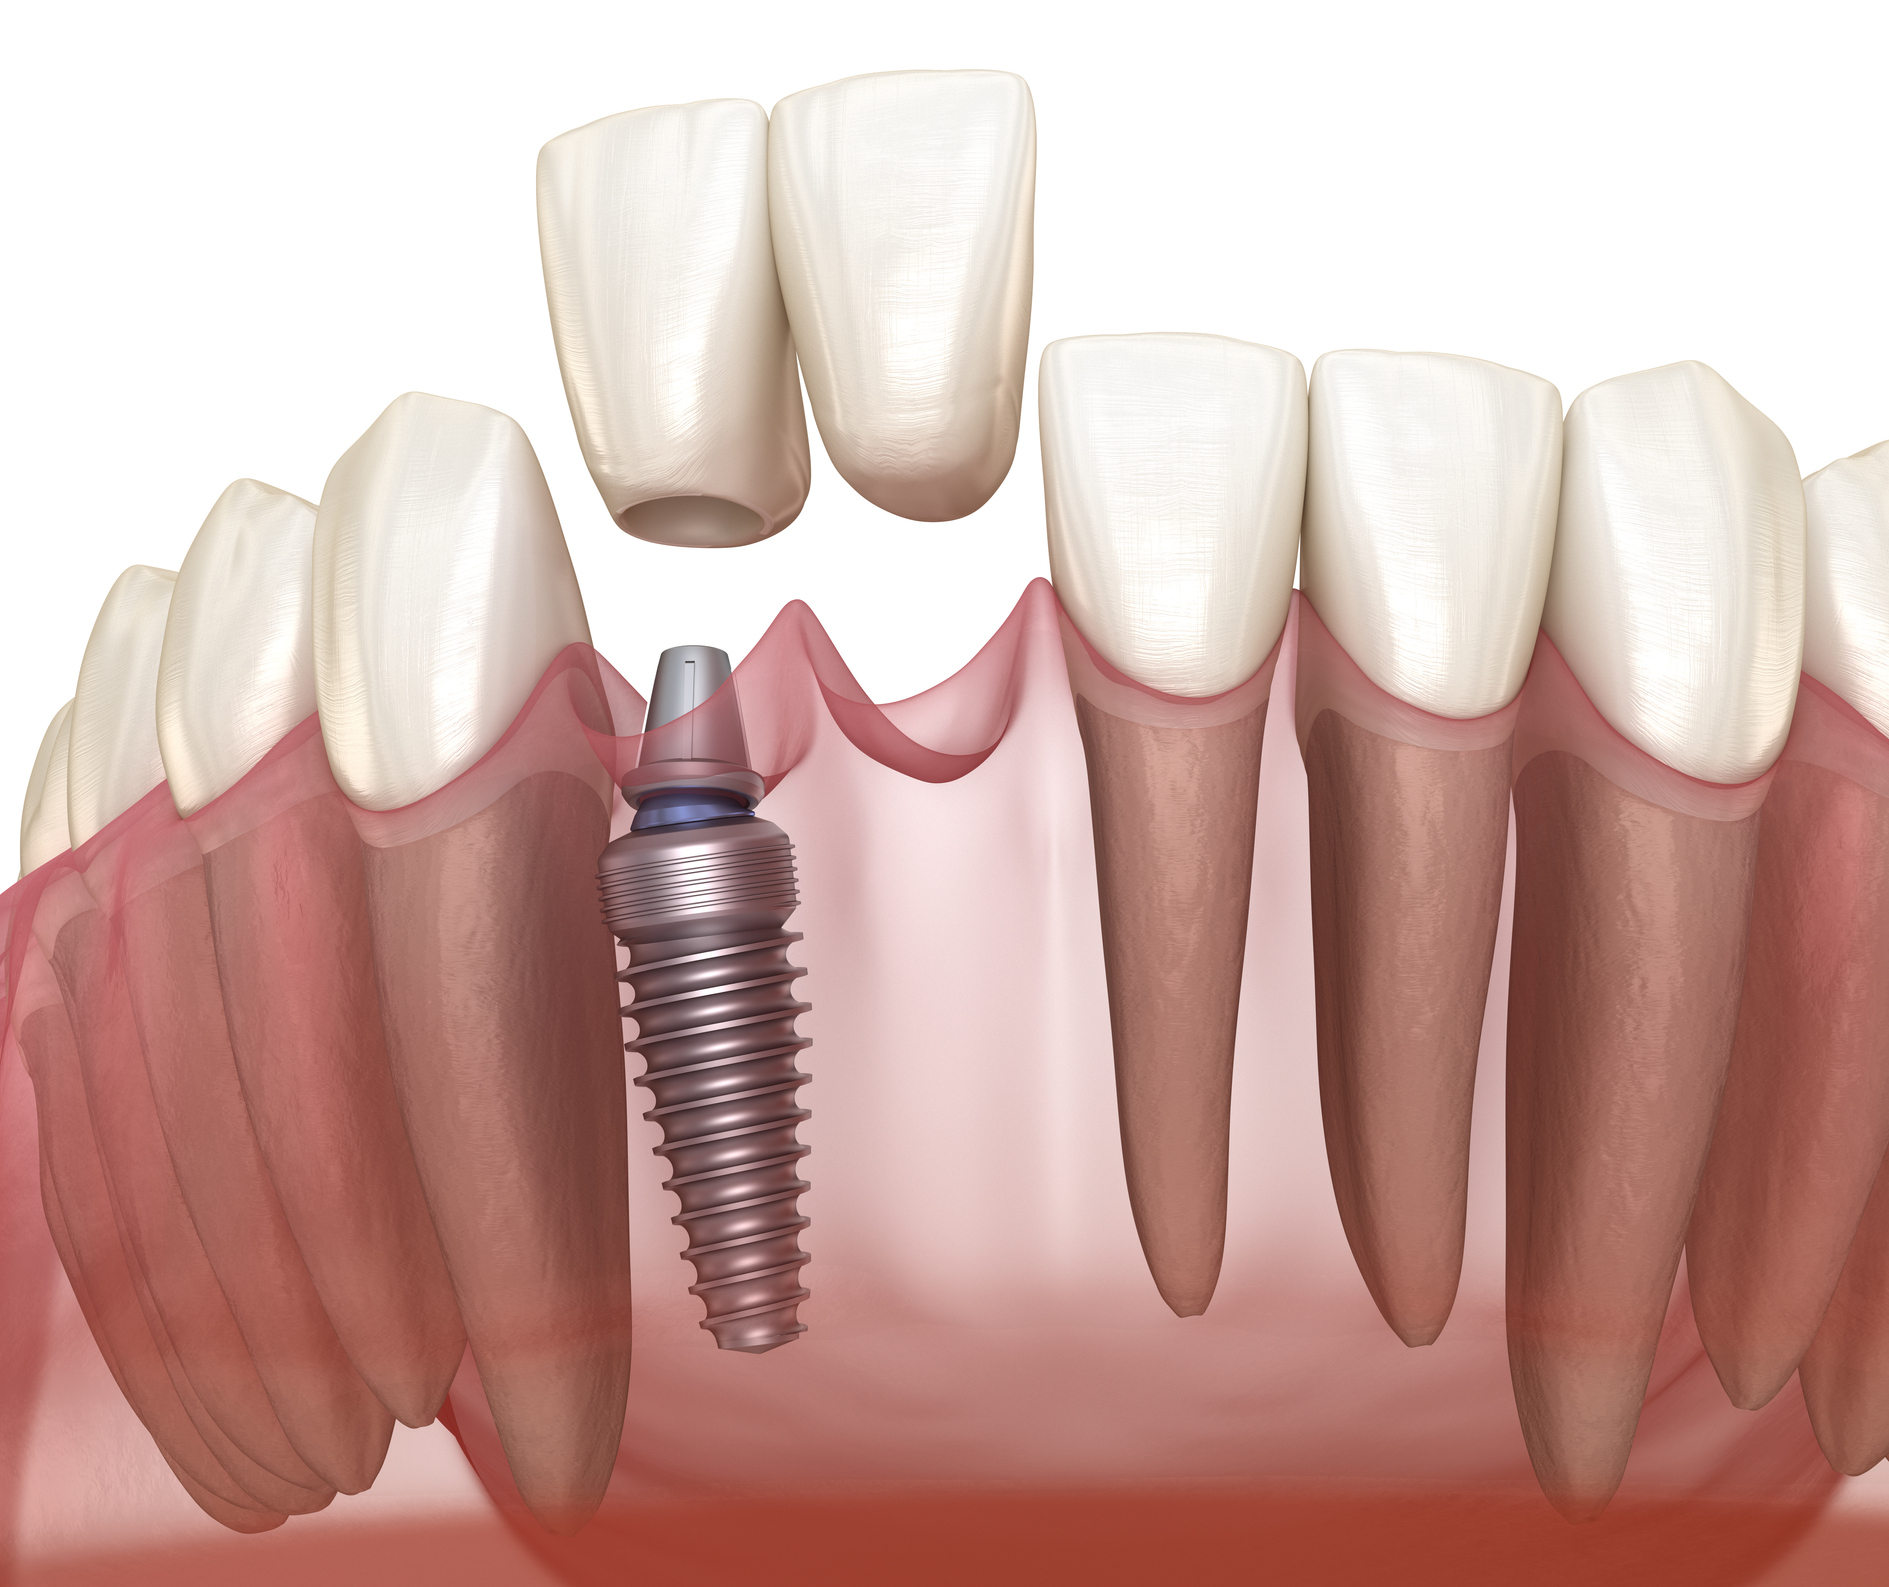

Single Teeth Implant

A permanent, natural-looking solution for replacing a missing tooth with precision.